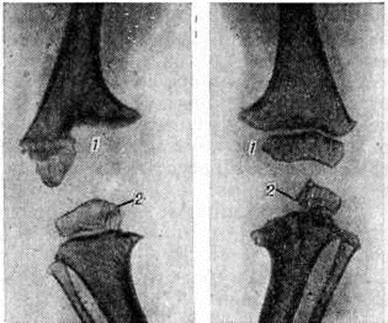

В других случаях наблюдается инкапсуляция гнойников в кости. К 3—4-й недель от начала заболевания при рентгенологическое исследовании на фоне рарефикации определяются очаги некроза кости, поскольку омертвевшая кость не подвергается резорбции и сохраняет прежнюю плотность. При патологоанатомическом исследовании участки некроза выявляются ещё раньше. В дальнейшем те из них, которые находятся в самом очаге нагноения, подвергаются секвестрации (рисунок 1). Секвестрация (смотри полный свод знаний Секвестр, секвестрация) заключается в отторжении омертвевших участков кости, находящихся в полости гнойника, от окружающей костной ткани. При этом в случае образования секвестра в компактной пластинке на её поверхности в зоне прилегания грануляций возникает и постепенно углубляется секвестральная борозда, а в толще — расширение гаверсовых каналов и слияние их между собой. После того как все костное вещество в указанной зоне растворится, секвестр оказывается свободно лежащим в полости гнойника (цветной рисунок 2 и 3). Секвестры губчатого вещества кости отделяются от остальной её части за счёт растворения прилежащих костных балок, находящихся в зоне грануляций (рисунок 2).

Рис. 2. | ||